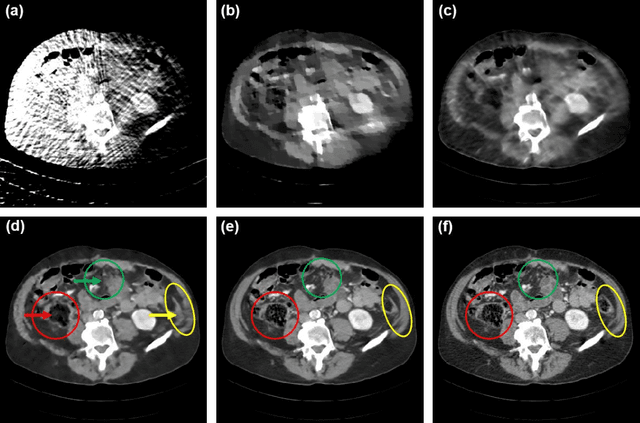

Abstract:By the ALARA (As Low As Reasonably Achievable) principle, ultra-low-dose CT reconstruction is a holy grail to minimize cancer risks and genetic damages, especially for children. With the development of medical CT technologies, the iterative algorithms are widely used to reconstruct decent CT images from a low-dose scan. Recently, artificial intelligence (AI) techniques have shown a great promise in further reducing CT radiation dose to the next level. In this paper, we demonstrate that AI-powered CT reconstruction offers diagnostic image quality at an ultra-low-dose level comparable to that of radiography. Specifically, here we develop a Split Unrolled Grid-like Alternative Reconstruction (SUGAR) network, in which deep learning, physical modeling and image prior are integrated. The reconstruction results from clinical datasets show that excellent images can be reconstructed using SUGAR from 36 projections. This approach has a potential to change future healthcare.